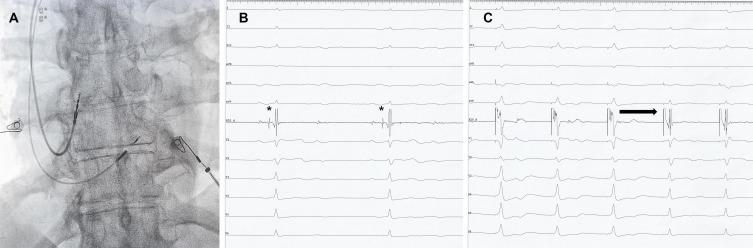

Although feasibility studies have included older patients, specific data for His bundle pacing (HBP) in this population is scarce. The aim of this study was to evaluate the feasibility and mid-term performance of HBP in the elderly (70 to 79 years old) versus the very elderly (80 years old and above) patients with conventional indications for pacing.

The procedural success rate was similar in both age groups (68.49% vs 65.62%). There was no significant difference in pacing or sensing thresholds, impedance, and fluoroscopy times. For both age intervals, patients with a baseline narrow QRS maintained a similar QRS duration after pacing, while in patients with a wide QRS, the paced QRS was significantly shorter. Baseline QRS duration, left bundle branch block morphology, and ejection fraction, were significantly associated with HBP procedural failure. The mean follow-up period was 830.34 days for the elderly and 722.76 days for the very elderly. After the follow-up period, both sensing and pacing thresholds were similar between the groups. Compared to the baseline values, there were no significant changes in both pacing and sensing parameters, irrespective of the age interval. During follow-up, no lead dislodgements were recorded. There were two cases of significant pacing threshold rise in the elderly (4%) and three cases in the very elderly group (14.2%) which were managed conservatively, without lead revision.

In elderly and very elderly patients, HBP is a feasible procedure associated with constant pacing and sensing parameters and with low complication rates over mid-term follow-up.